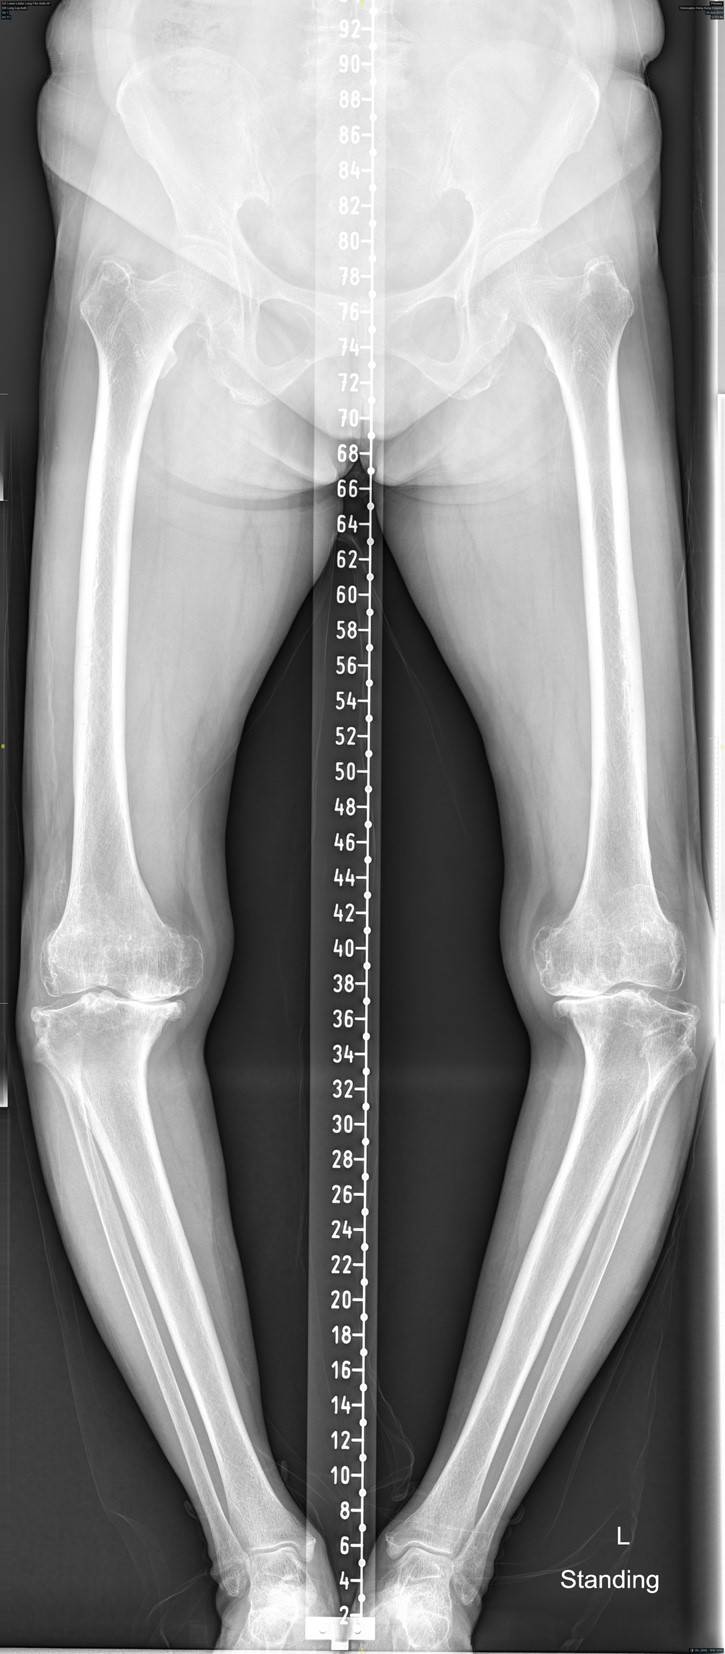

When the degeneration becomes more severe, the cartilage may be worn down completely. This is accompanied by underlying bone erosion, ligament laxity, joint capsule instability, and inflamed and swollen synovium. The degenerated joint may become irregular and develop bone spurs (osteophytes).

Patients may experience joint stiffness, inability to flex or extend, or develop deformity, resulting in "O-shaped feet". The range of motion of the joint is reduced, making it impossible to stand for long periods of time and causing weakness especially upon walking up stairs or squatting. Upon environment temperature change or upon movement, your joints will experience severe pain, making it difficult to move. These symptoms not only cause inconvenience in the patient's work and daily life, but also have the potential to impact their emotional well-being.

The doctor then will arrange patient to an X-ray imaging. On the X-ray, the doctor will specifically look for signs of joint space narrowing and soft tissue swelling. If you are already experiencing symptoms of joint pain, it is recommended to consult a professional medical doctor promptly to seek appropriate treatment.